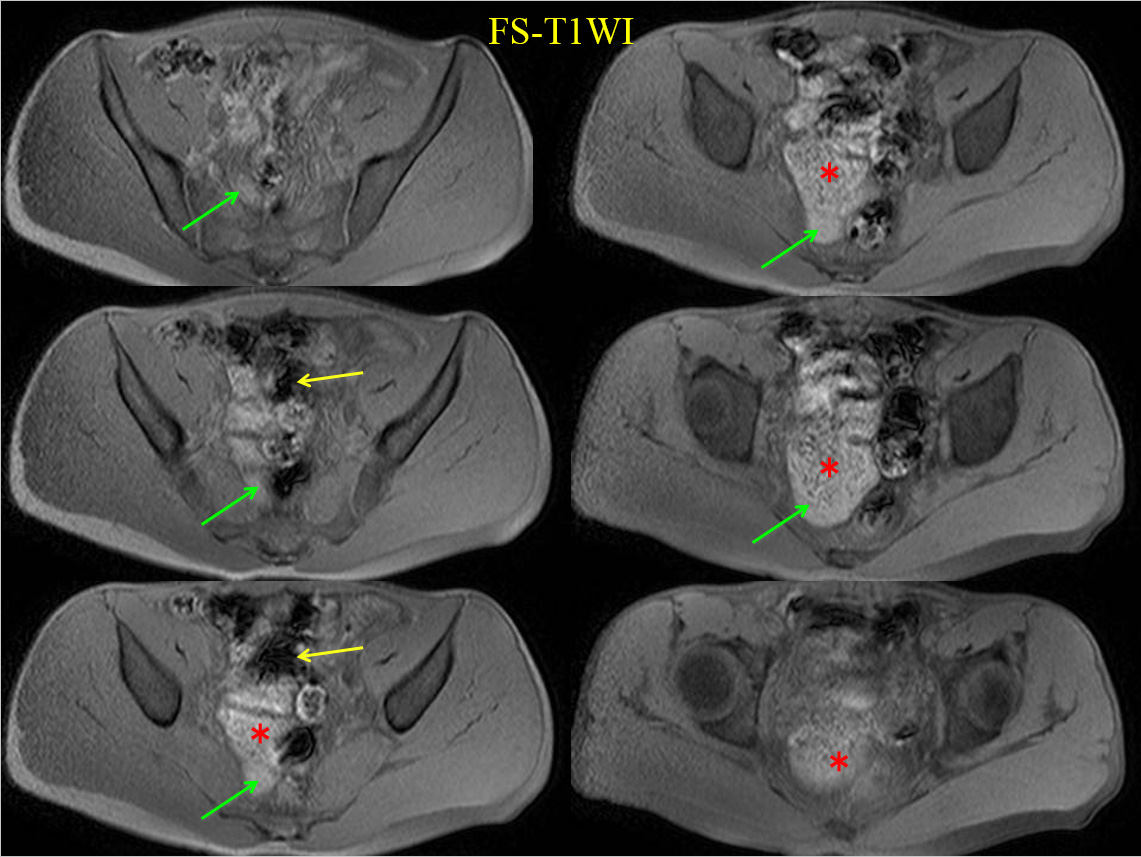

• FS-T1WI

MRでは、骨盤内に大きな嚢胞性病変を認める。

すなわちT2WI、T1WIでいずれも高進号を呈すが、脂肪抑制で抑制されず、造影で辺縁部のみわずかに濃染される。

内部には不均一で貯留物があると認識されるが、血性を示唆する所見には乏しい。

骨盤内の嚢胞性病変の鑑別となるが、男性であるため卵巣由来は否定的である。水平断像および冠状断像を丹念に読影すると、同病変は小腸と連続しており、腸管構造の一部であることがわかる。病変の局在は回腸末端に近く、年齢、経過を加味すると、メッケル憩室が最も考えられる。